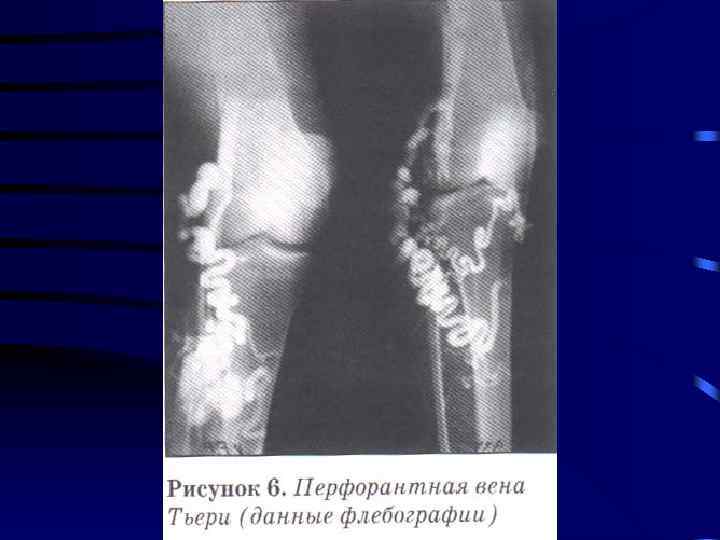

Диагностика: 1. Клиника 2. УЗИ сосудов 3. Дуплексное сканирование 4. Флебография